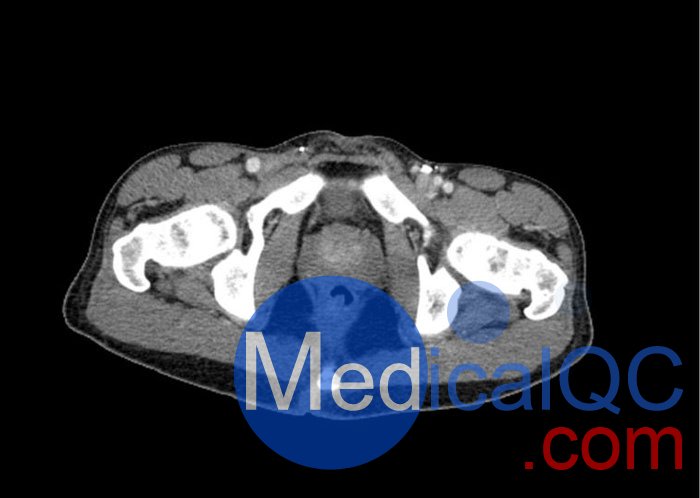

WEK57-01門靜脈期軀干模體,WEK57-01軀干模型模擬了門靜脈期的造影劑增強(qiáng)胸部、腹部和骨盆。它覆蓋了會陰的第二胸椎。

右側(cè)有髂淋巴結(jié)腫塊。

真實模擬脈管系統(tǒng)、骨骼和軟組織,包括肺、心臟、肝臟、膽囊、胰腺、脾臟、腎上腺、腎臟、胃、小腸、結(jié)腸、膀胱和前列腺。

右側(cè)髂外淋巴結(jié)腫塊。

WEK57-01門靜脈期軀干模體,WEK57-01軀干模型成像效果圖: